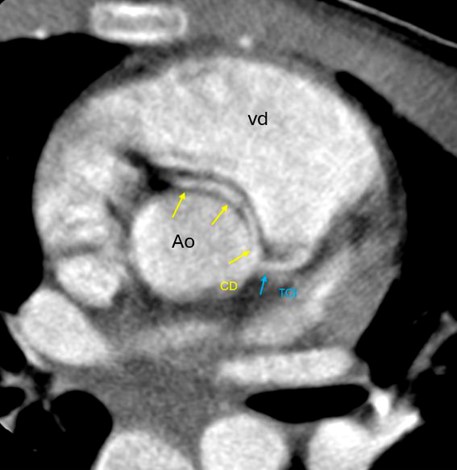

La angiotomografía coronaria demostró un origen anómalo de la arteria coronaria derecha a partir del seno coronario izquierdo, con trayecto interarterial entre la aorta y el tronco de la arteria pulmonar, asociado a una reducción aproximada del 50% del calibre en su segmento proximal (Fig. 1). Adicionalmente se observó leve dilatación difusa del tronco coronario izquierdo y del segmento proximal de la arteria circunfleja, sin evidencia de aneurismas ni estenosis en los segmentos medio y distal (Figs. 2 y 3).

Figura 1. Angiotomografía computarizada de arterias coronarias con corte axial a la altura de los grandes vasos, que muestra arteria coronaria derecha (CD) con origen del seno coronario izquierdo, trayecto interarterial que reduce su diámetro en más de un 50% con respecto al segmento siguiente. No se observan zonas de estenosis o dilataciones en los segmentos medio, distal y DP. Vd: ventrículo derecho, Ao: aorta abdominal, CD: coronaria derecha, TCI: tronco coronario izquierdo, DP: arteria descendente posterior.